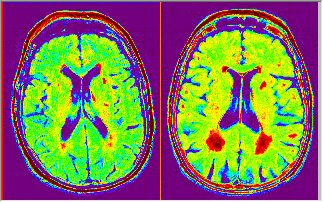

Image Palette

A gray scale image can be color-mapped to a palette. Pseudo color does not add additional information to the original image. However, it helps to make some details more visible to human eyes. It is commonly used for viewing sensor images, such as satellite images and Magnetic Resonance Imaging.

| Original Image | Image with a Palette |

To Map a Color Palette to a Cray Scale Image,

- With the gray scale image window active, click Palette button

on the Style toolbar and select a palette from the drop-down list.

OR,

- With the image window active, run

cvPalette -d;in the Command Window (Window: Command Window or Shift+ALT+3) to open the cvPalette dialog. - Pick a color palette to apply to the image.

You can click Revise Palette button |